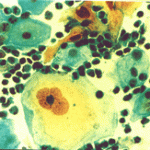

Περιστατικό ασθενούς που παρακολουθείται στο ιατρείο μας από το 1993, τότε ηλικίας 37 ετών, αρχικά λόγω ασυμπατωματικού κυτταρολογικά εμμένοντας έρπητος τραχήλου της μήτρας. Το γεγονός αυτό μας οδήγησε στην διερεύνηση της περιπτώσεως. Η ασθενής επασχε από A.I.D.S.

Είχαμε την ευκαρία να παρακολουθήσουμε ανά 6μηνο γυναικολογικά, κολποσκοιπικά και κυτταρολογικά την γυναίκα από το 1993 μεχρι και το 2008. Από τις εξετασεις αυτές, παρουσιάζουμε χαρακτηριστικές κυτταρολογικές εικόνες . Όι παρακάτω κυτταρολογικές εικονες προέρχονται από την 2η κατά σειρά εξέταση της ασθενούς το 1993. Οι κυτταρολογικές αλλοιώσεις ερπητος συνεχίζουν να υφίστανται.

Ταση γιγαντιοκυττάρωσης όλων των επιθηλιακώ στοιβάδων, κοιλοκυττάρωση, διογκωμένοι υπερχρωματικοί και ανισομεγέθεις πυρήνες , με διάλυση δομής χρωματίνης, συχνά διογκωμενοι πυρήνες με εικόνα φαινομένου ΄΄θολού γυαλιού΄΄